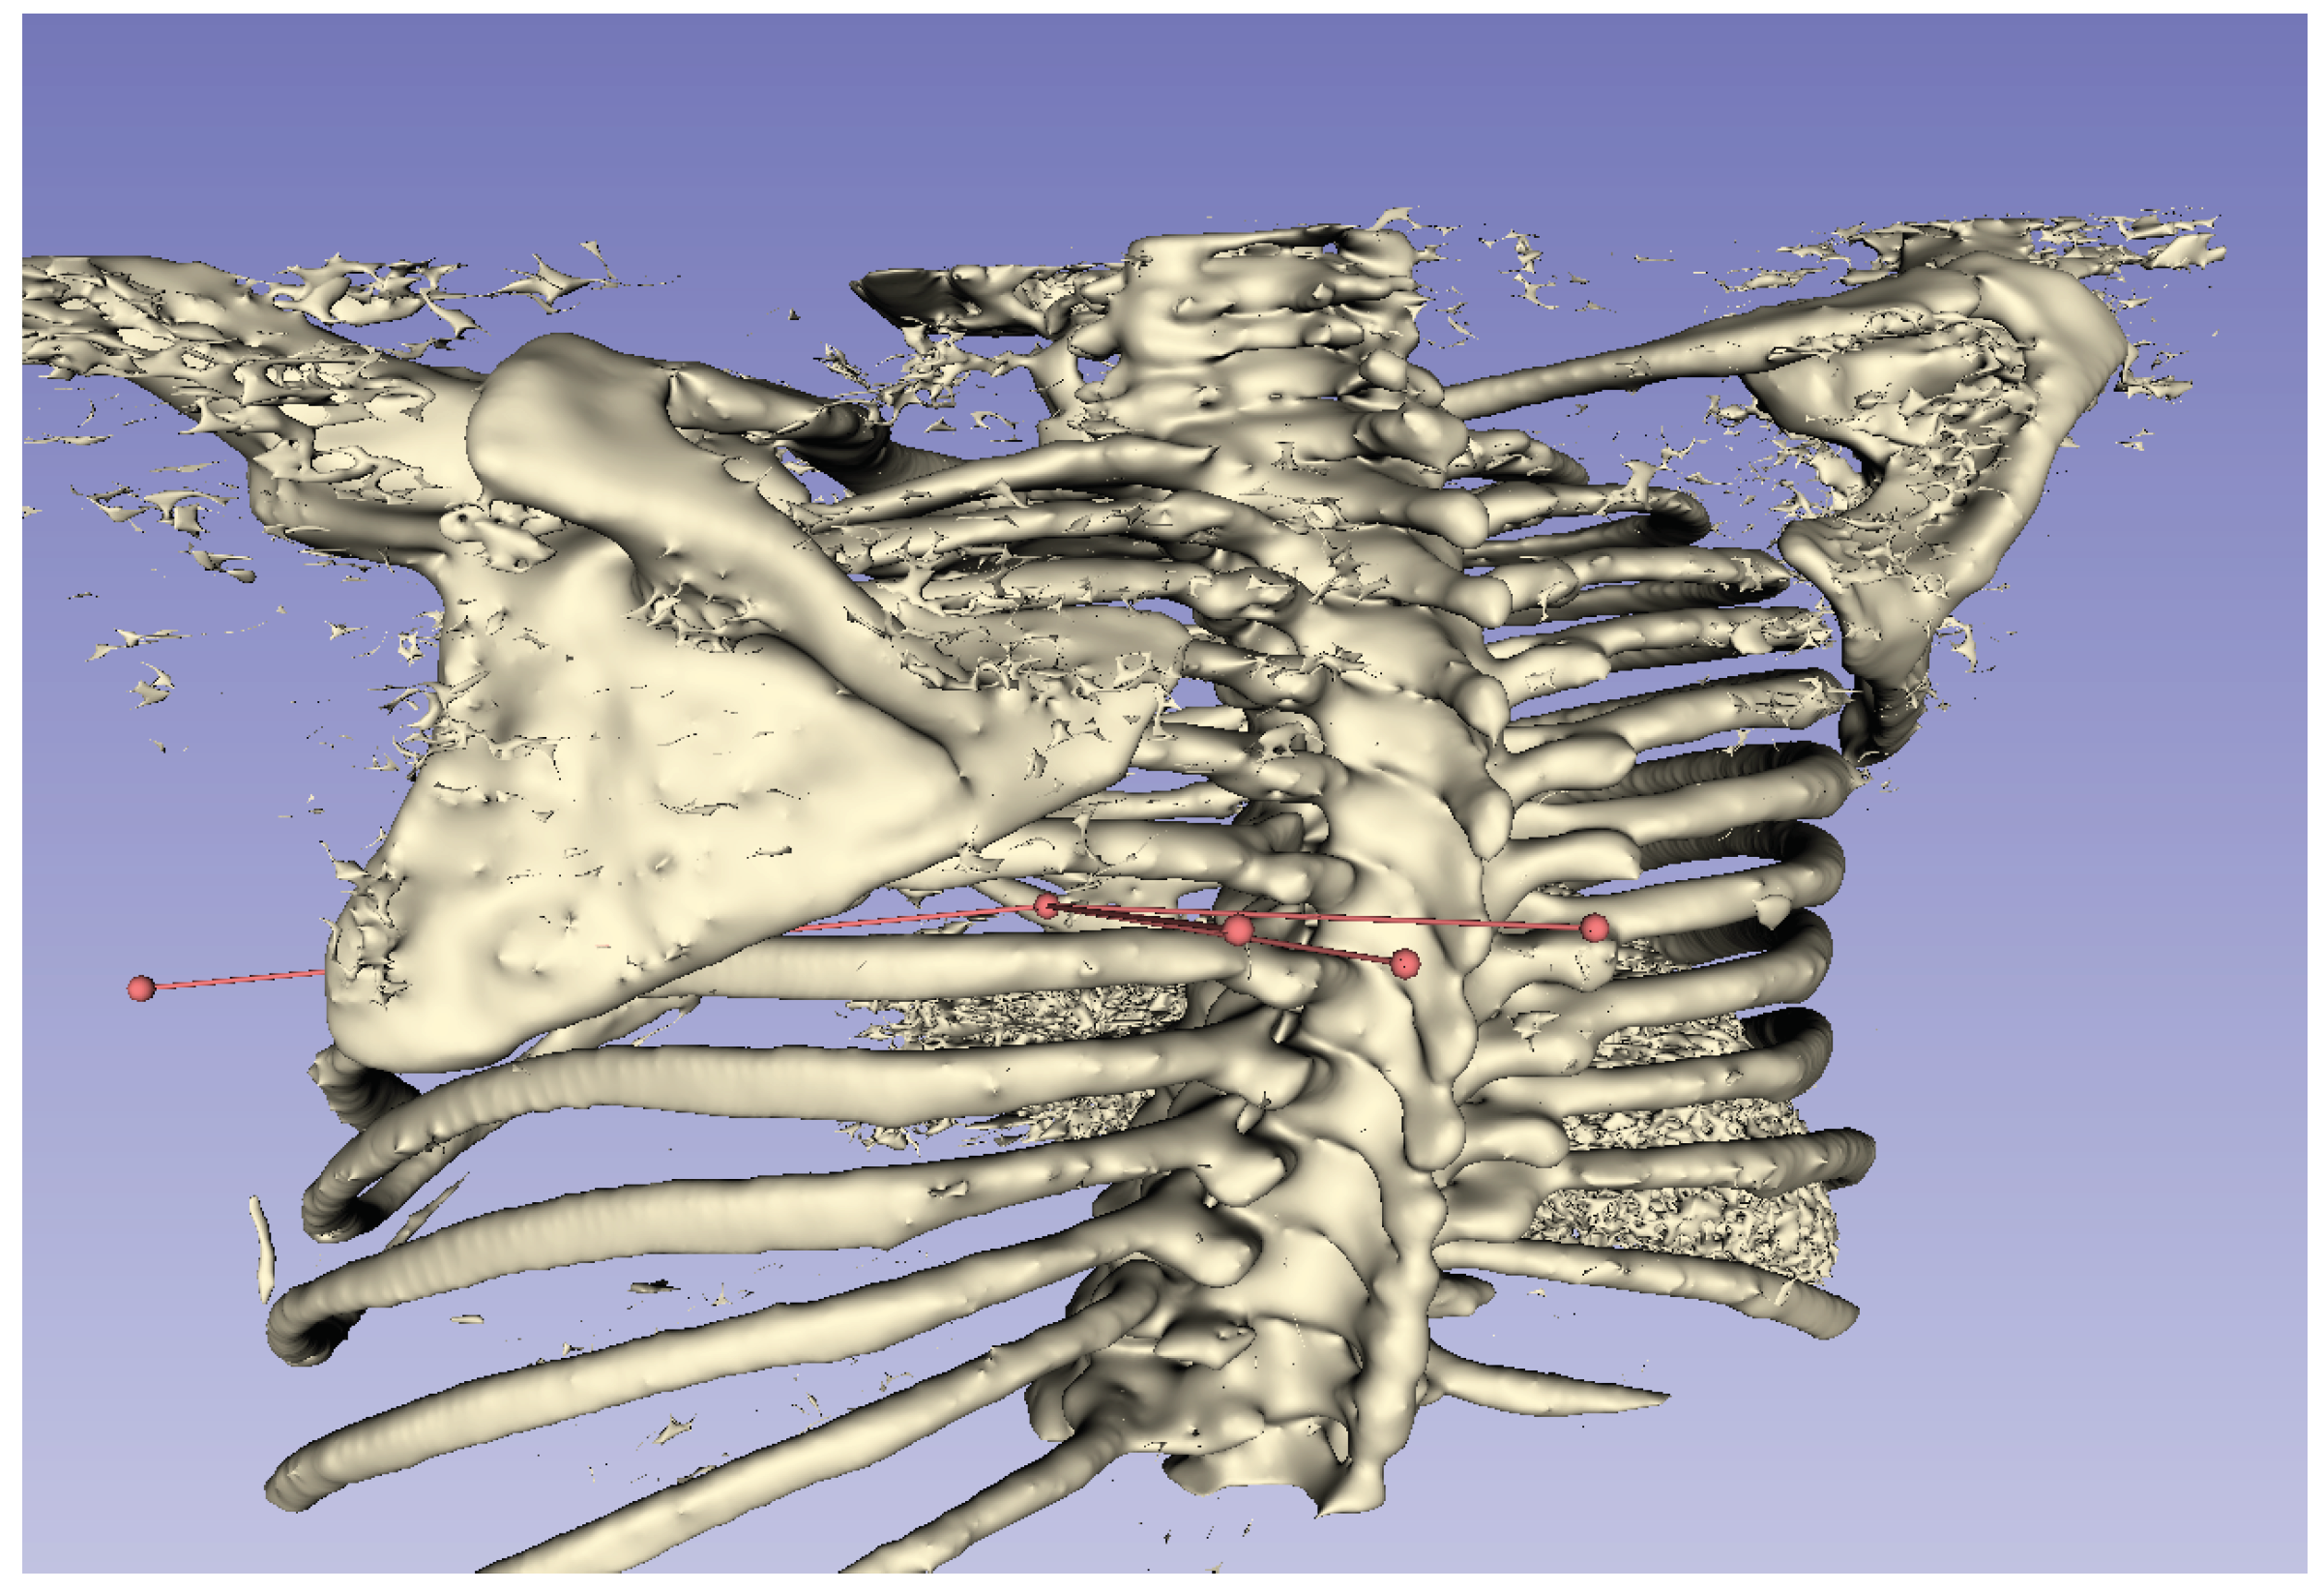

By visualizing the line segment from the target to the coordinates of the puncture start position as a three-dimensional image, a physician can easily determine the puncture route. In this study, we used the 3D Slicer [19] application to visualize the puncture route. An example display of a CT image using the 3D Slicer is shown in Figure 7. 3D Slicer is open source software that can construct three-dimensional images from DICOM data.

6.2. Processing Time to Derive Puncture

Figure 10 shows the puncture routes derived by the proposed method. The red spheres in the figure are the start and end points of the puncture, and the line connecting the two red spheres is the puncture route. In this evaluation, the human body was composed of 170 two-dimensional CT images, and these images were superimposed to create a three-dimensional CT image. The processing time required to derive the puncture route for a three-dimensional CT image using all 170 two-dimensional CT images was approximately 59.4 s.

For the puncture targets T 1 and T 2 , the visualization of the puncture routes are shown in Figure 11 and Figure 12, respectively. These figures show that all puncture routes pass through the bone, indicating that they are not puncturable routes.

Figure 7. Example of a CT image using 3D Slicer.

Figure 10. Example of three-dimensional puncture route.